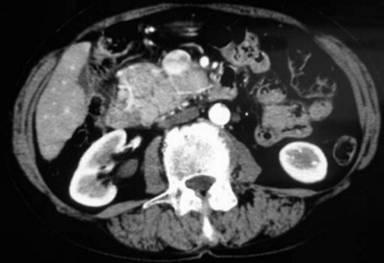

She underwent upper digestive endoscopy and endoscopic ultrasound (EUS) which revealed the presence of a large, solid mass localized in the pancreatic head, infiltrating the duodenal wall. A cytological examination of the lesion under EUS guidance was negative for neoplastic cells. A new CT scan revealed an enlargement of the pancreatic mass (9x5x8 cm in diameter) with infiltration of the duodenum (Figure 1).

|

Figure 1. Abdominal CT scan showing a large and solid mass (9x5x8 cm in diameter) located in the head of the pancreas. |